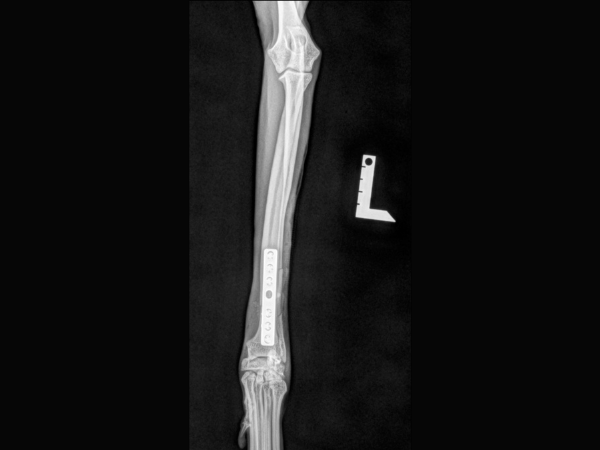

<術前のレントゲン>

左橈尺骨遠位端が骨折しています。